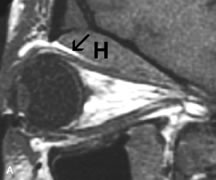

Breast carcinoma metastatic to the orbit has been demonstrated to be hypointense to the surrounding orbital fat on T1-weighted studies and hyperintense on T2-weighted images and has an affinity to the extraocular muscles (Fig. 20).50,64 The MRI characteristics of prostate carcinoma metastatic to the orbit have been described as involving the greater and lesser wing of the sphenoid, orbital roof, and optic canal. Diffuse bone hypertrophy with isointense or slightly hyperintense tissue on T1-weighted images represents the osteoblastic carcinomatous bone infiltration. Contrast enhancement is variable on T1-weighted and fat-suppressed images.65

Fig. 20. A. T1-weighted MR scan demonstrates nodular enlargement of both medial rectus muscles (arrows). B. T1-weighted fat-suppressed contrast-enhanced scan confirms the presence of small metnstatic deposits within the muscles (open arrows).